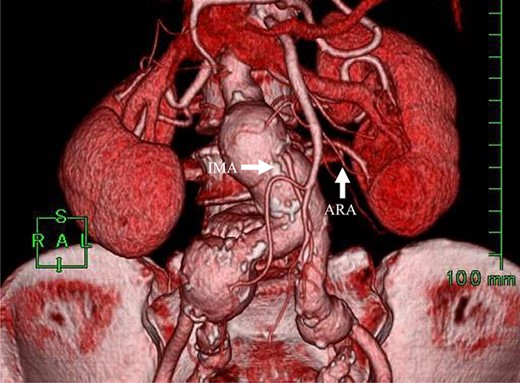

Angiography for decision-making revealed a type II endoleak from the IMA to the AAA, but no other visible endoleak (Fig. 2). Based on these findings, we planned additional EVAR for left CIAA, which was thought to have enlarged in natural course, and IMA embolization for the type II endoleak associated with sac enlargement. A staged strategy was devised. IMA embolization was planned several days after EVAR. Sac angiography from the IMA via Riolan’s arcade showed a flow-through endoleak to the ARA as a drainage artery (Fig. 3). Based on this finding, we embolized the ARA and the IMA with coils via Riolan’s arcade (Fig. 4). Selection and embolization of the drainage artery were technically feasible because of the flow from the IMA to the ARA. No deterioration of renal function due to ARA embolization was observed. One year after treatment, a CT scan demonstrated that the sac shrank to 42 mm with no evidence of a continuing endoleak (Fig. 5).

Angiography 8 years after EVAR demonstrated a type II endoleak from the IMA.